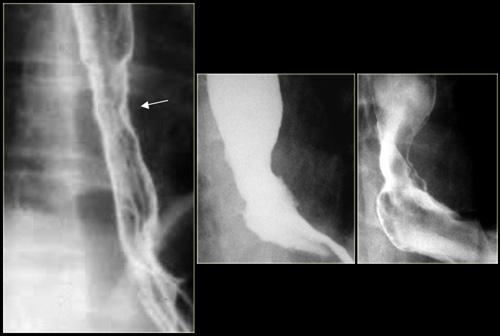

Hình ảnh ngoài cùng bên trái cho thấy vị trí hẹp (mũi tên) với các nếp niêm mạc không đều tại vùng hẹp trên hình ảnh đối quang không khí.

Bệnh nhân này được chẩn đoán thực quản Barrett.

Hẹp và loét thực quản đoạn giữa cần nghi ngờ thực quản Barrett.

Hai hình ảnh bên phải cho thấy thực quản Barrett với vùng hẹp không đều do ung thư biểu mô tuyến.

Hình bên trái cho thấy đoạn hẹp ở vị trí cao (mũi tên) sau khi nuốt phải chất ăn mòn.

Hình ảnh của bệnh nhân mắc pemphigoid lành tính.

Các bóng nước niêm mạc đã dẫn đến hình thành nhiều đoạn hẹp (mũi tên).

Hình ảnh của bệnh nhân mắc ly thượng bì bọng nước lành tính.

Các đoạn hẹp đa ổ (mũi tên) là di chứng của bệnh lý bọng nước niêm mạc.